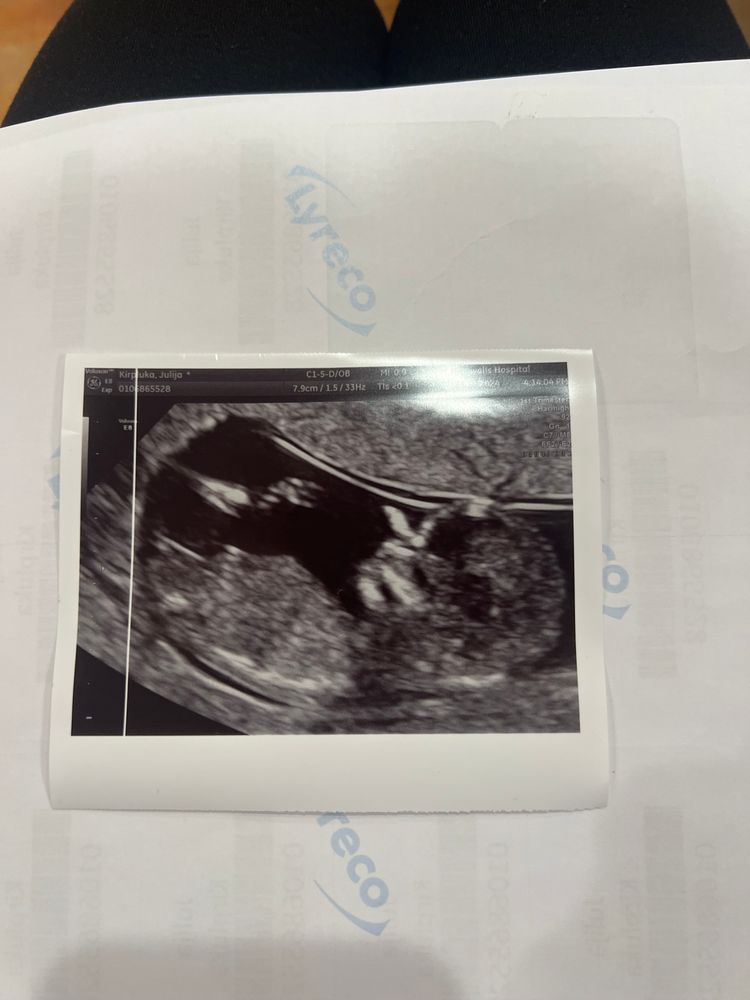

Девочки как думаете мальчик или девочка?

Срок маленький и ракурс плохой, но я за девочку🎈

Ну вообще тут не видно, ракурс как то не очень) ну если то что видно за бугорок рассматривать - то больше на девочку похоже.